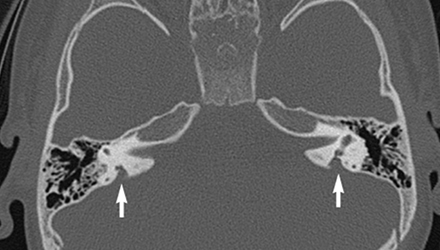

SLC26A4基因定位于人類染色體7q31,SLC26A4基因和大前庭導(dǎo)水管綜合征相關(guān)突變位點(diǎn)的發(fā)現(xiàn),證實(shí)SLC26A4是大前庭導(dǎo)水管綜合征的責(zé)任基因。

我們平時提到的“一巴掌打聾”、“一跤摔聾”其實(shí)都與SLC26A4基因突變有關(guān),絕大多數(shù)大前庭導(dǎo)水管綜合征都是SLC26A4基因突變?nèi)堑牡湣?/p>

SLC26A4基因編碼一種叫“Pendrin”的跨膜轉(zhuǎn)運(yùn)蛋白,在機(jī)體離子成分平衡的維持中發(fā)揮重要作用。

在內(nèi)耳,Pendrin表達(dá)于內(nèi)淋巴管、內(nèi)淋巴囊、橢圓囊、球囊等處,異變的蛋白將對這些結(jié)構(gòu)的正常生理功能產(chǎn)生影響,引發(fā)聽損。

聽力損失表現(xiàn):

SLC26A4基因突變導(dǎo)致的大前庭導(dǎo)水管綜合征的典型表現(xiàn)為兒童時期的聽力損失,90%的患者為雙側(cè)性,聽力損失程度不一,可表現(xiàn)為接近正常或重-極重度。

病程可為穩(wěn)定性、進(jìn)行性或波動性,聽力可逐步下降至全聾;跌倒、撞擊等行為或無外界影響都可能引發(fā)聽力的下降。